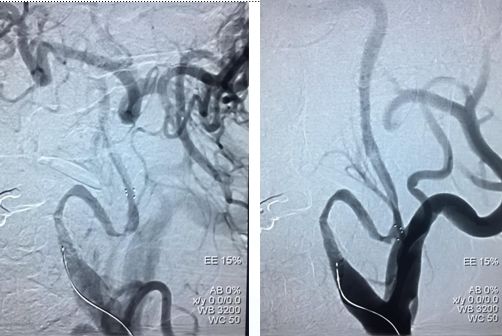

右椎V4段狭窄,2.5*15球囊扩张(应用替罗非班)

13:40:应用3.0*13Apollo支架释放血管再通

自觉头晕、头沉,BP90/60mmHg,嗜睡,精神稍差,言语不清,四肢肌力、肌张力正常,双侧Babinski征(-)。

NIHSS评分2分。